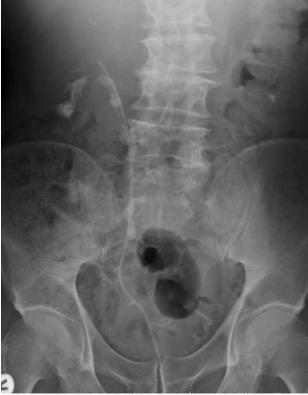

Figure 1

68Ga prostate specific membrane antigen (PSMA) PET/CT: presence of high suspicious area fo prostate cancer (SUVmax 20) in both lobe of the prostate (axial evaluation)

was performed from the skull base to the middle of the thigh Images were processed to obtain PET, CT, and PET CT fusion sections in the axial, coronal, and sagittal planes with a thickness of approximately 0 5 cm by two experienced nuclear medicine specialists, who were blinded to the clinical data The location of focal uptake on 68Ga PSMA PET/TC (Figure 1), three dimensional size, and standardised uptake value (SUVmax) values were reported on a per lesion basis with a sexstant scheme (apex, midgland, and base, each split into left and right) (5) All mpMRI (Prostate Imaging Reporting and Data System “PI RADS” version 2 ≥ 3) and 68GaPSMA PET/CT (SUVmax > 5 g/ml) index lesions underwent targeted cores (mpMRI TPBx and PSMA TPBx: four cores) com bined with extended systematic prostate biopsy (eSPBx: median 18 cores) (2, 14) The procedure was performed transperineally using a tru cut 18 gauge needle (Bard, Covington, GA, USA) under sedation and antibiotic pro phylaxis (17) Prostate targeted cores were obtained using a Hitachi 70 Arietta echograph (Chiba, Japan) supplied by a bi planar trans rectal probe (14) by one urologist with 10 years of experience in cognitive targeted biopsy Data were collected following START criteria (18)